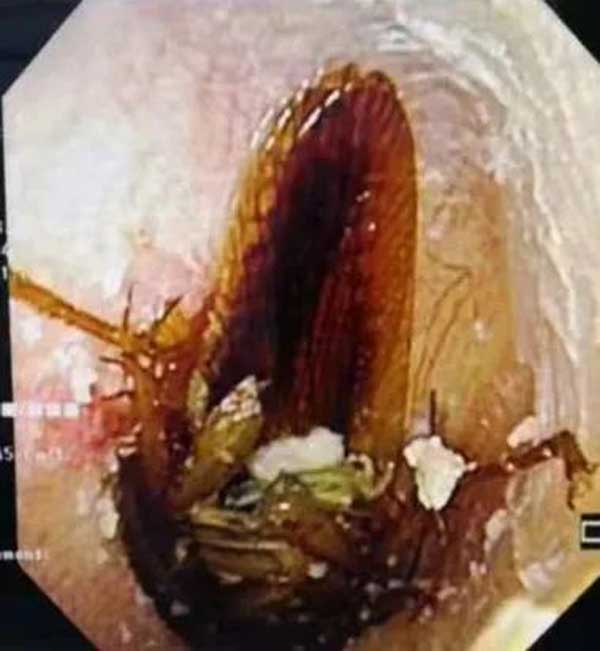

跑进耳朵里的小飞虫

次日一大早,3岁的阳阳就被妈妈带到了德州扑克游戏网 耳鼻喉科。经过检查,跑进阳阳右耳朵里的是一只小飞虫,所幸虫子位置不深。在安抚了阳阳的情绪后,副主任李莉萍用镊子小心地夹出了一只指甲盖大小的活体飞虫。她说:“幸亏孩子没有用力掏耳朵,不然很可能造成鼓膜穿孔,影响孩子听力。”